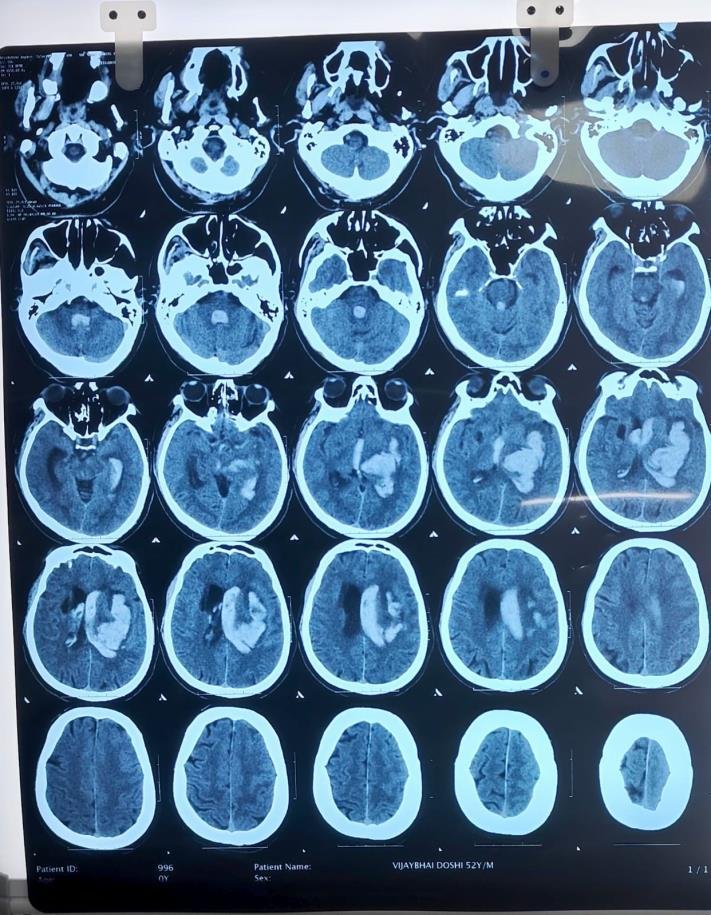

CT Scan Findings

Acute large intraparenchymal bleed in the left gangliocapsular region, corona radiata, and left fronto-parietal lobe.

Size: 41 × 57 × 60 mm (CC × AP × TR).

Mild perilesional edema causing mass effect with 6.7 mm midline shift to the right.

Intraventricular extension of bleed into both lateral ventricles, third, and fourth ventricles.

Mild periventricular ooze → suggestion of developing hydrocephalus.

Mild cerebral edema.